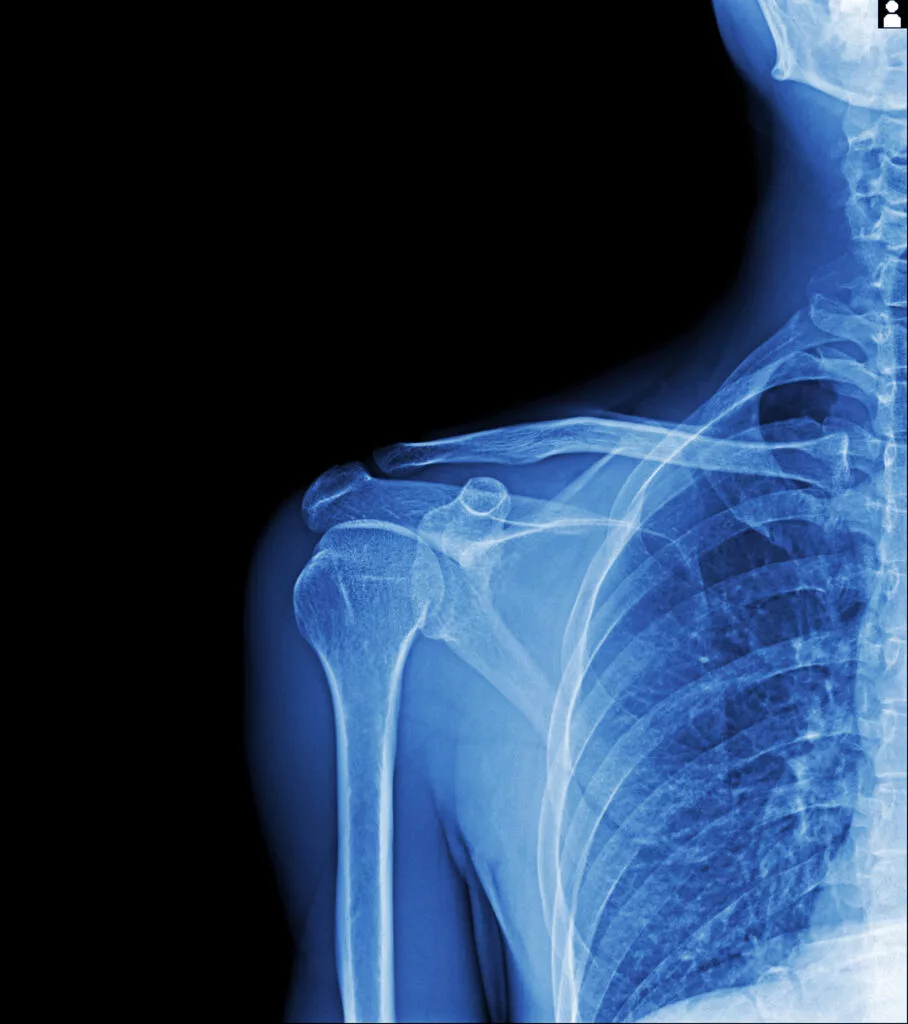

Your doctor will begin with a physical exam to assess pain and range of motion. You may be asked to move your arm in different directions, or the doctor may move it for you to check passive motion.

In some cases, imaging tests are done to rule out other conditions like arthritis or rotator cuff injuries:

| X-ray | Rules out bone problems or arthritis |

| MRI | Checks soft tissues like tendons and ligaments |

| Ultrasound | Helps detect inflammation or fluid buildup |